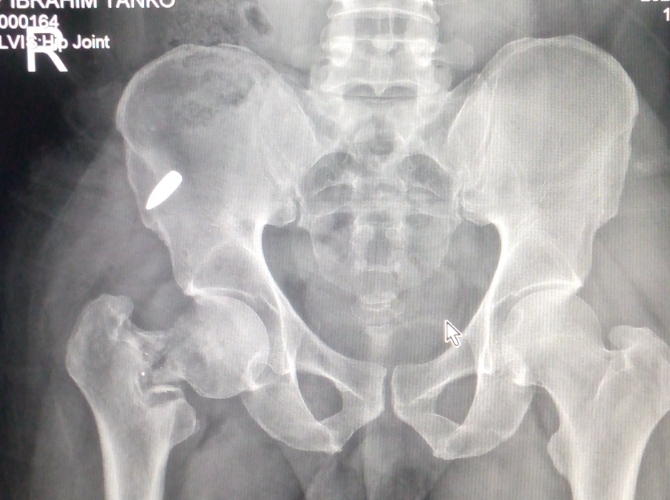

My name is Ibrahim Tanko, a serving Nigerian police officer.

In the course of my official duty, I was shot by bandits, which resulted in a serious injury to my right thigh. Sadly, after almost one year, a metal fragment is still lodged in my thigh, causing persistent pain and medical complications.

Medical reports and supporting documents are available.